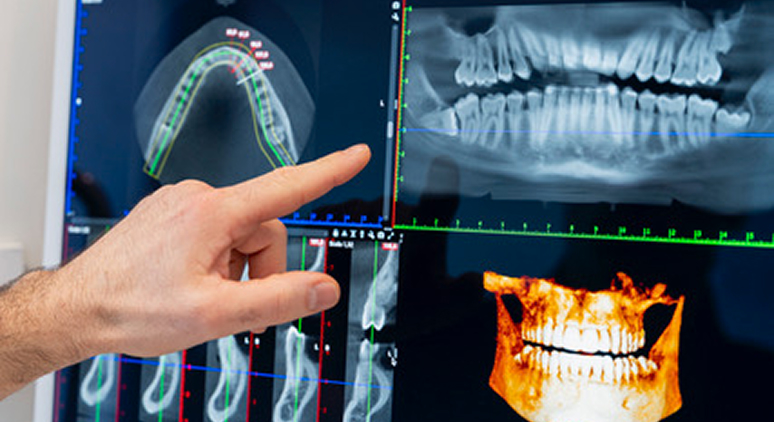

La chirurgia orale è una branca Specialistica dell’odontoiatria che comprende gli interventi chirurgici volti a risolvere patologie e problematiche complesse del cavo orale. Tra questi i più frequenti sono le estrazioni dentali tra cui quelle dei denti del giudizio, l’asportazione di cisti o neoformazioni, l’eliminazione dei frenuli, il recupero di denti in inclusione ossea totale (ad esempio i canini permanenti), l’asportazione di apici radicolari compromessi, rigenerazioni ossee in caso di deficit significativi, corticotomie per favorire la mobilitazione

dentale durante alcuni trattamenti ortodontici.Tali interventi, che in alcuni casi possono risultare particolarmente articolati, richiedono una diagnosi accurata e dettagliata. Oggi, grazie all’utilizzo delle più avanzate tecnologie diagnostiche, come le radiografie in 3D, è possibile ottenere una visualizzazione tridimensionale precisa delle strutture anatomiche, consentendo una pianificazione chirurgica ottimale e riducendo al minimo i rischi legati all’intervento.

L’impiego di immagini 3D avanzate per lo studio del caso e la pianificazione pre-operatoria consentono di eseguire interventi chirurgici con un approccio minimamente invasivo e significativamente più sicuro. L’analisi dettagliata delle strutture anatomiche permette di ridurre al minimo i rischi anche nei casi chirurgici più complessi, ottimizzando i risultati e favorendo una gestione post-operatoria più efficace.